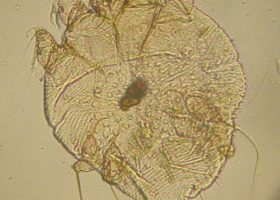

A new study investigates the effectiveness of mass drug administration to reduce prevalence of mites that cause scabies and their… Read more »